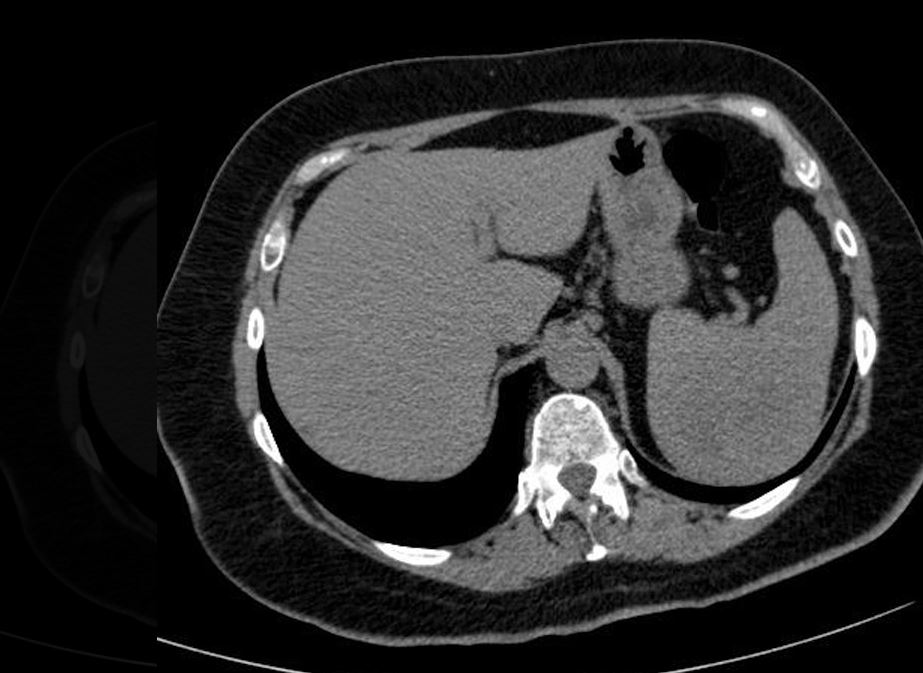

Η ασθενής δεν είχε σημαντικό ιατρικό ιστορικό και οι εργαστηριακές εξετάσεις της ήταν κανονικές. Η αξονική τομογραφία κοιλίας αποκάλυψε, ωστόσο, μία μεγάλη μάζα στον σπλήνα. Πραγματοποιήθηκε σπληνεκτομή και η ιστοπαθολογική ανάλυση αποκάλυψε φλεγμονώδη μυοϊνοβλαστικό όγκο.

Το όργανο είχε υποστεί μία ελαφρά μεγέθυνση. Οι τομές που έγιναν αποκάλυψαν νεκρωτικές περιοχές, ενώ δεν παρατηρήθηκαν μακροσκοπικές ανωμαλίες στο υπόλοιπο σπληνικό παρέγχυμα.